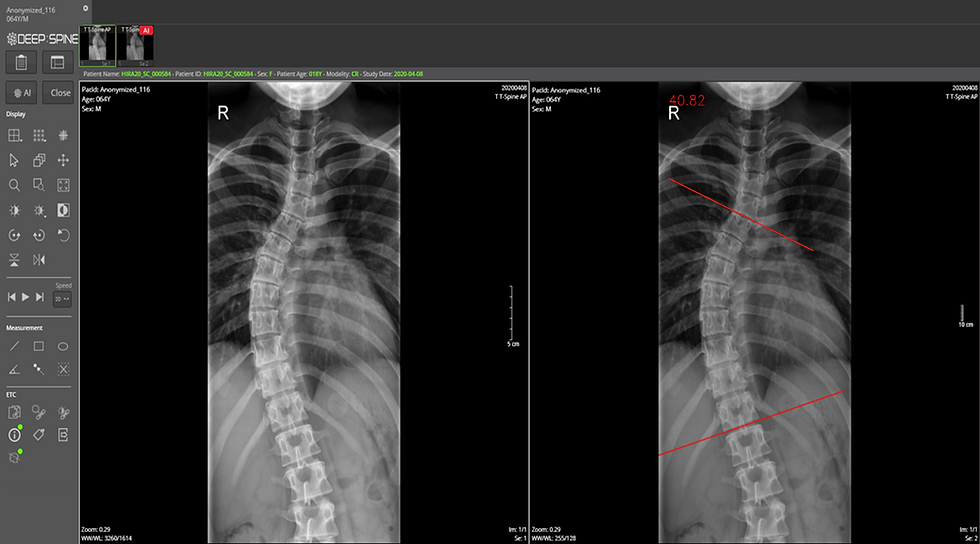

의료 인공지능 플랫폼 전문기업 딥노이드는 최근 의료 인공지능 기술과 자사의 PACS(의료영상저장전송장치) 기술을 활용한 척추질환 자동 진단 및 분석 시스템을 건강보험심사평가원에 구축 완료했다.

해당 시스템은 인공지능으로 의료영상을 판독해 척추질환의 더욱 정확한 심사가 가능하도록 지원하며, 척추측만증, 척추압박골절과 같은 질환의 유무 및 중증도 측정값을 자동 분석하는 게 특징이다.